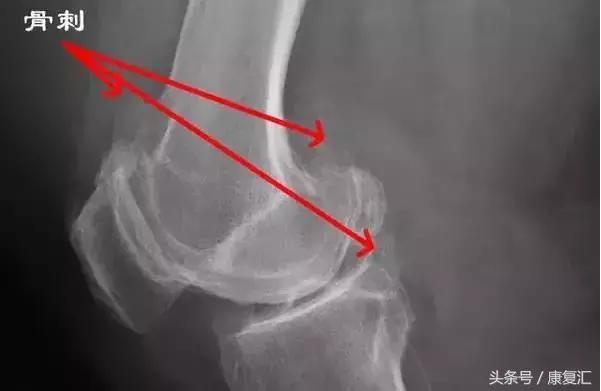

骨刺也被称为骨质增生、骨赘,是正常的骨头多长出来一部分,有相当一部分人会有骨质增生,其中又以膝关节最为常见;

其实非常简单,一张普通的X线片子就能看出来有没有长骨刺,比如膝关节,只需要拍一张膝关节正侧位片子即可。